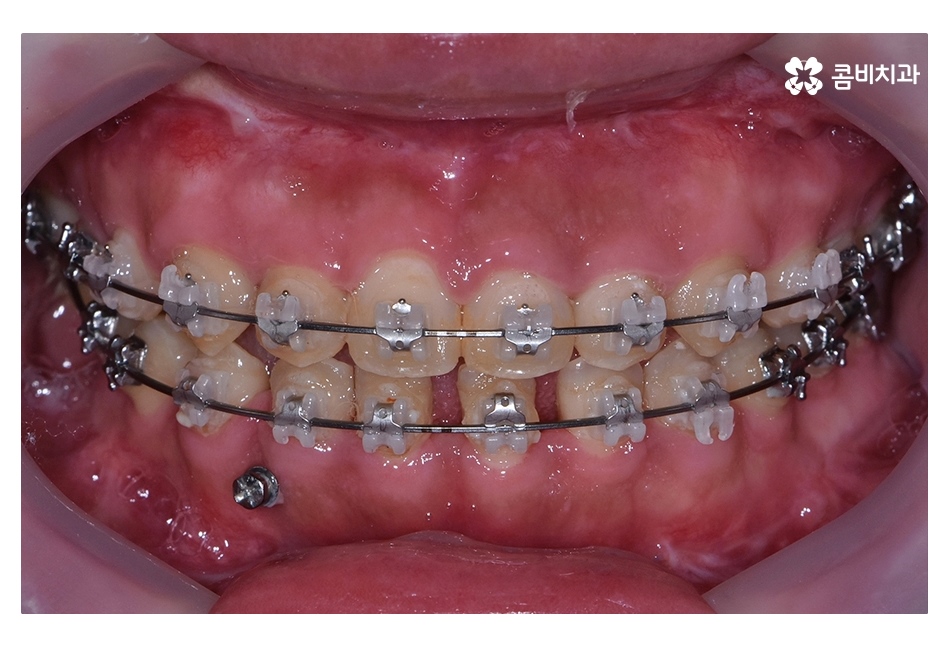

오늘 보시는 사례는 아랫니가 윗니를 덮고 있는

반대교합의 상태로 음식을 제대로 씹지 못하고

발음이 부정확하며 심미적으로도 좋지 않기 때문에

치아교정을 통해 치료가 필요한 케이스 중 하나라고 볼 수 있어요

클리피씨교정이 진행되고 시간이 지날수록 아랫니가

점점 윗니에 덮이는 정상 교합의 상태로 개선되는 것을 볼 수 있는데요.

교정 후 교합이 정상적으로 맞물리는 것을 확인할 수 있어요.